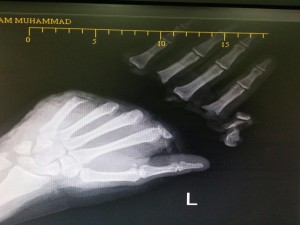

صورة الأشعة ليد المريض قبل العملية

نجح مجموعة من من الأطباء في مستشفى خولة وتحديدا قسم جراحة اليد مؤخرا في تحقيق انجاز مهم تمثل في إجراء عملية معقدة لزراعة أربعة أصابع مبتورة بقطع كامل لعامل من الجنسية الآسيوية في العقد الثالث من عمره بعد تعرضه لإصابة عمل قبل عدة ايام. واستغرقت عملية زراعة الاصابع المبتورة حوالي 16 ساعة متواصلة. ولله الحمد تكللت ساعات العمل الطويلة والمتواصلة عن إعادة زراعة الأصابع بكل نجاح. وعبر المريض عن شكره العميق للطاقم الطبي على اسعافه ورعايته، وشكر زملائه الذين أنقذوه، وكفيله الذي وقف معه وقفة انسانية نبيلة وتكفل بكامل مصاريف العلاج.